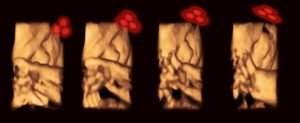

شاهد الباحثون، باستخدام التصوير رباعي الأبعاد بالموجات فوق الصوتية، كيف تفاعلت الأجنة التي يبلغ عمرها 34 أسبوعا لرؤية مثلثات قريبة من شكل الوجه (نقطتين فوق وواحدة تحت)، مقارنة برؤية شكل مثلث قائم (القاعدة تحت ونقطة أعلى الوجه)، حيث قاموا بعكس ضوء أحمر في شكل مثلث -في كلتا الوضعيتين المذكورتين آنفًا- فوق بطن الأم اعتمادًا على الرؤية المحيطية للجنين، بعدها مرّروا الضوء فوق بطن الأم، بعيدًا عن مرمى نظر الجنين، لمعرفة ما إذا كان سيُدير رأسه لمواصلة النظر إلى الصورة (الضوء الأحمر).

عرض الباحثون مثلثات مختلفة خمس مرات لـ 39 جنين، وحركت الأجنة رؤوسها 40 مرة لرؤية مثلث قريب من شكل الوجه، من بين 195 عرض لمثلثات على شكل وجه. وفي المقابل، وفقًا لما ذكره الباحث المشارك في الدراسة من جامعة لانكستر بإنجلترا ”فنست ريد”، حركت الأجنة رؤوسها 14 مرة فقط لرؤية أشكال مثلثات مخالفة لشكل الوجه.